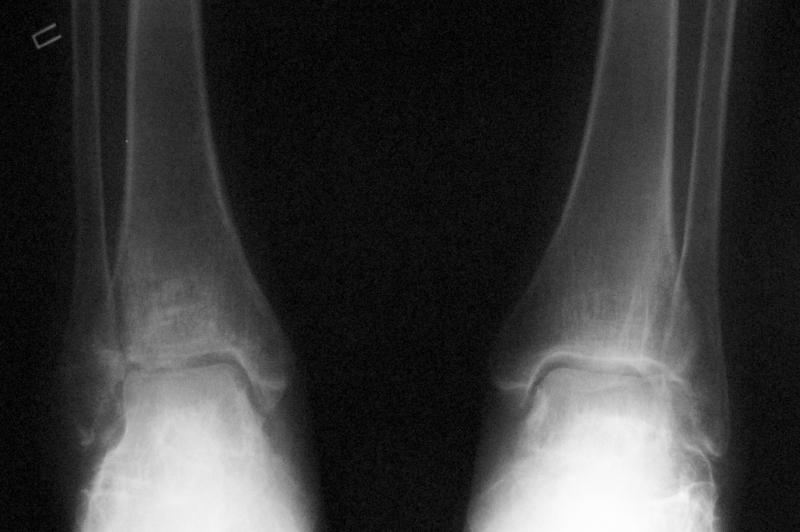

Уважаемые коллеги! Помогите определится с тактикой лечения. Оскольчатый импрессионный перелом заднего края правой большеберцовой (Пилон?) кости 5-ти недельной давности на фоне неправильно сросшихся переломов пяточных костей (травма в 1991г.), ДОА подтаранных суставов 3 ст.

До последней травмы больная ходила без особых проблем и работала пекарем (работа на ногах). Суть проблемы в том, что открытая анатомическая репозиция в таком сроке представляется мне крайне травматичной, что может привести к неблагоприятному функциональному исходу. Варианты решения: 1) оставить "как есть" с последующим артродезом после развития ДОА 2) выполнить остеотомию и попытаться низвести основную часть суставной поверхности 3) выполнить попытку анатомической репозиции из задне-латерального??? доступа.